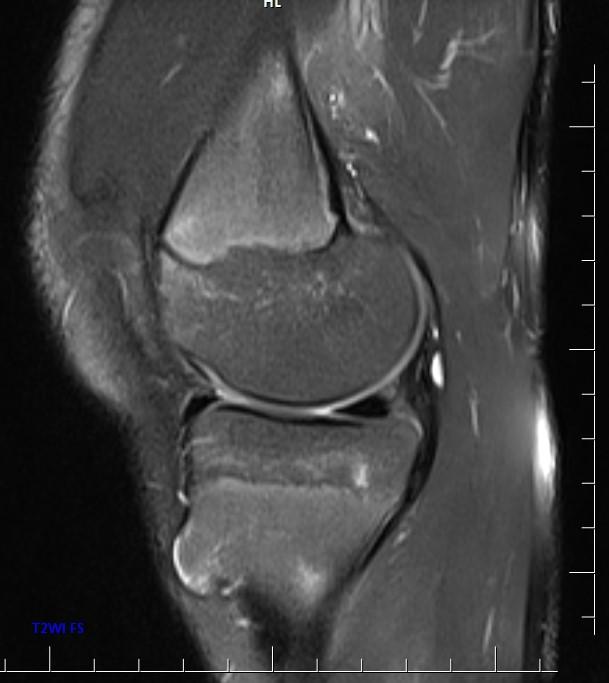

*13-year-old boy with mass on the proximal tibia.

Answer: Osteochondroma

MR images show osteochondroma on the proximal tibia.

MRI is the best imaging procedure to evaluate cartilage thickness, presence of edema in bone or adjacent soft tissues, and visualizing neurovascular structures in the vicinity.

The cartilage cap appears the same as cartilage elsewhere, with intermediate to low signal on T1WI and high signal on T2WI. The cartilage cap of over 1.5 cm in thickness is suspicious for malignant degeneration. The cartilaginous cap itself should not enhance.